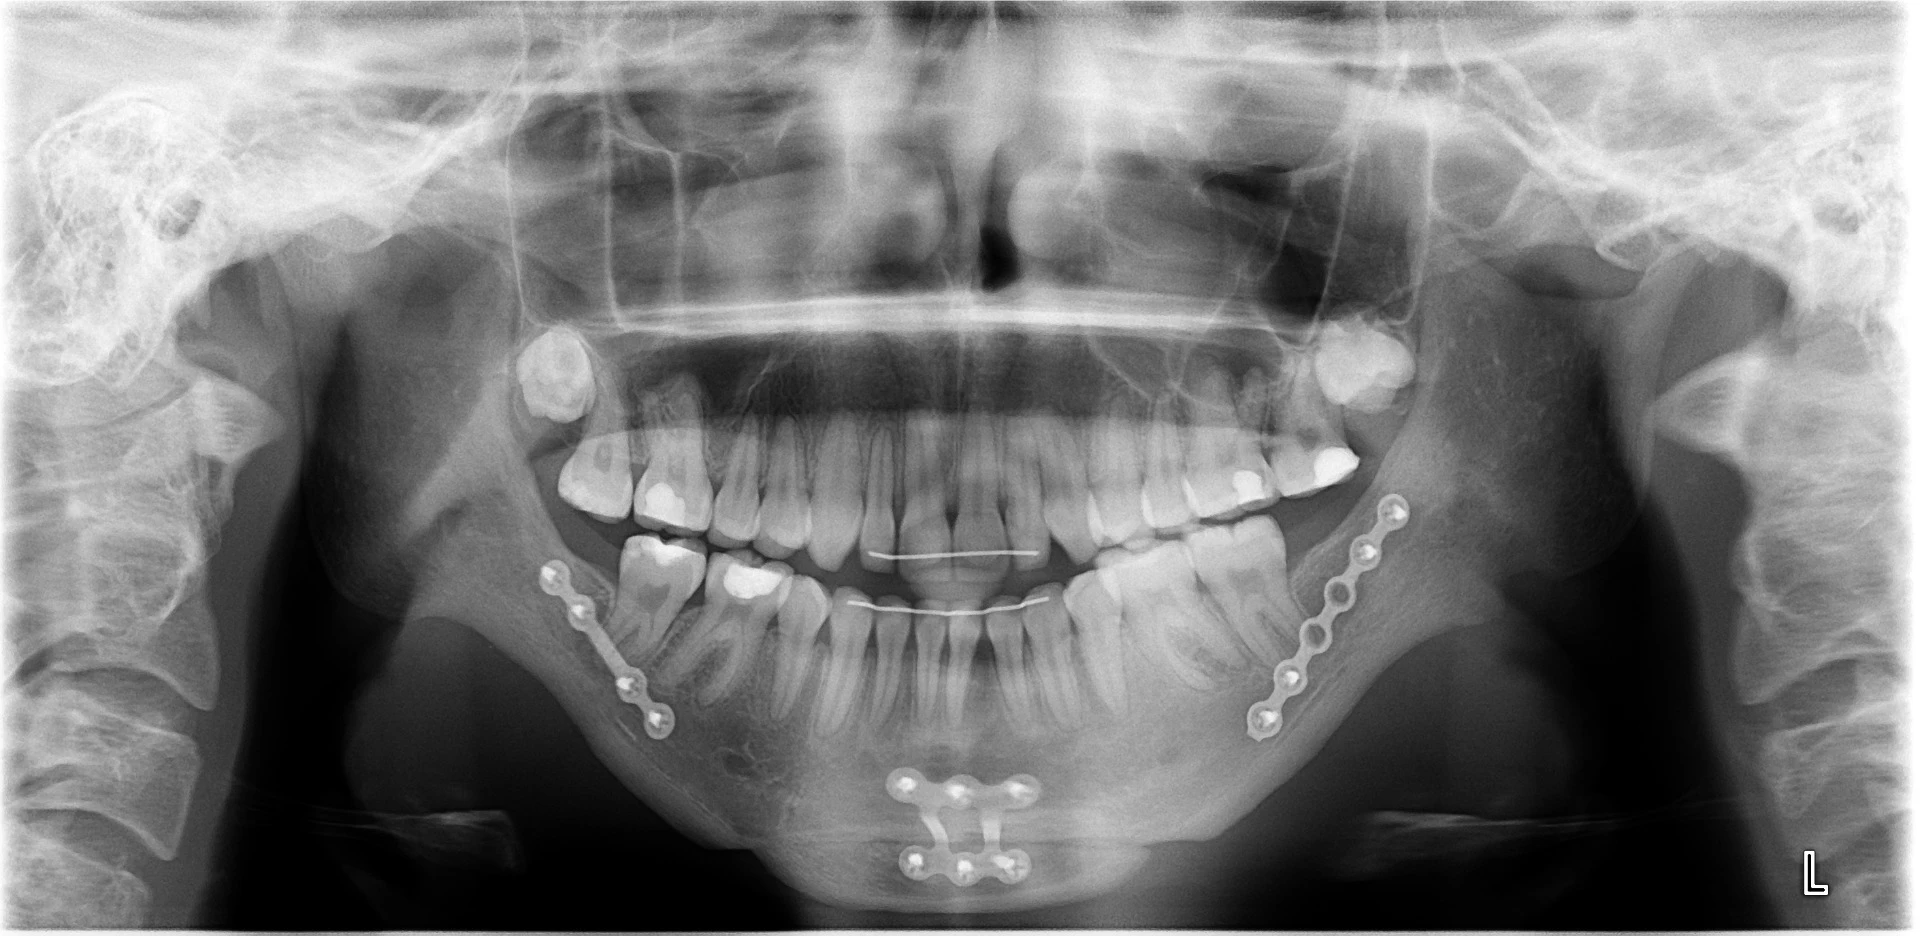

Vårt arbeid

Alle pasienter som vises har gitt skriftlig samtykke til at bildene kan brukes på klinikkens nettside.